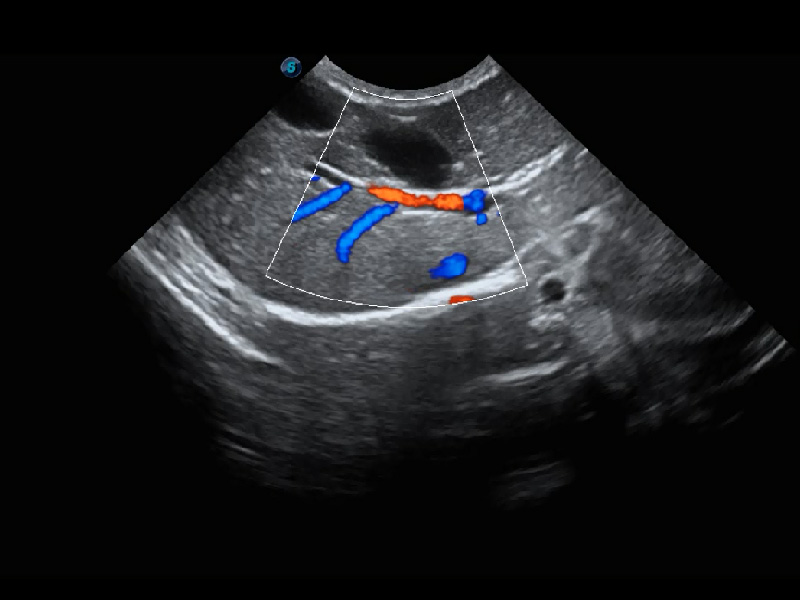

ProPet 60 作為一款高端臺式動物超聲設備,為動物醫(yī)生的日常診斷提供了一系列貼合動物臨床需求、解決臨床實際問題的高級成像功能。憑借全系列高清探頭,滿足醫(yī)生對腹部、心臟、生殖、淺表、肌骨等成像的所有需求,切實幫助您提升檢查效率,提高診斷信心。

獸用彩色多普勒超聲診斷系統(tǒng)